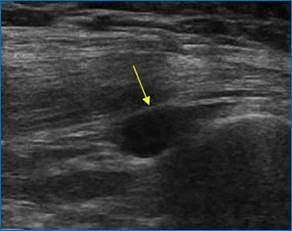

Зачастую может быть обнаружен выпот в полости того или иного сустава (рис. 1).

Рис. 1. Выпот в полости сустава, утолщение синовиальной оболочки